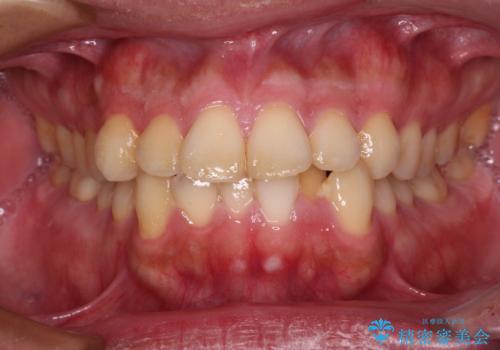

- 前歯のデコボコを治したいとのことで来院された患者様です。

できる限り楽して、短期間で治したいとのことで、ワイヤー装置にて矯正治療を行うこととしました。